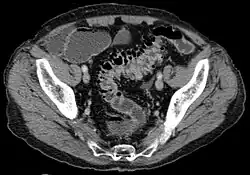

Diverticulosis in the sigmoid colon of a 70-year-old